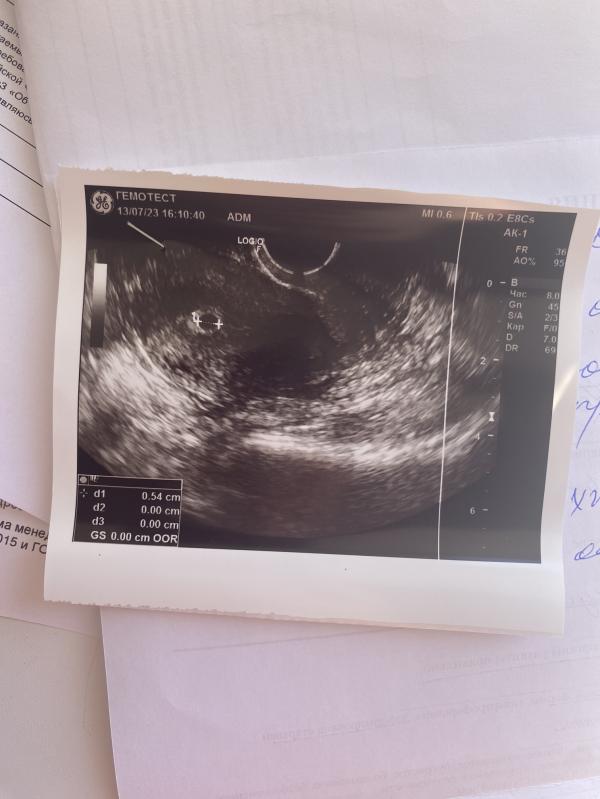

Сделала тест не знаю зачем и он положительный 2 четкие полоски. Сделала узи и сдала хгч, хгч был 322 11.07.2023г и узи в тот же день нашли плодное яйцо, у врача шок как так если цикл только начался. Сдала повторно 14.07 пришел сегодня результат 889. И была на повтор узи выложу фото. Эндометрий был тонкий и назначили дюфостан 2 р д, пью. Повтор узи в понедельник и сдам еще раз хгч.

Боялась что внематочная, хорошо что маточная. А теперь боюсь что может быть замершая так как рост хгч мало растет. Должен был быть выше 1200. Большая путаница у меня у сроке😭 кто с таким сталкивался ?

Интересно, как вам нашли плодное яйцо при хгч 322 ???